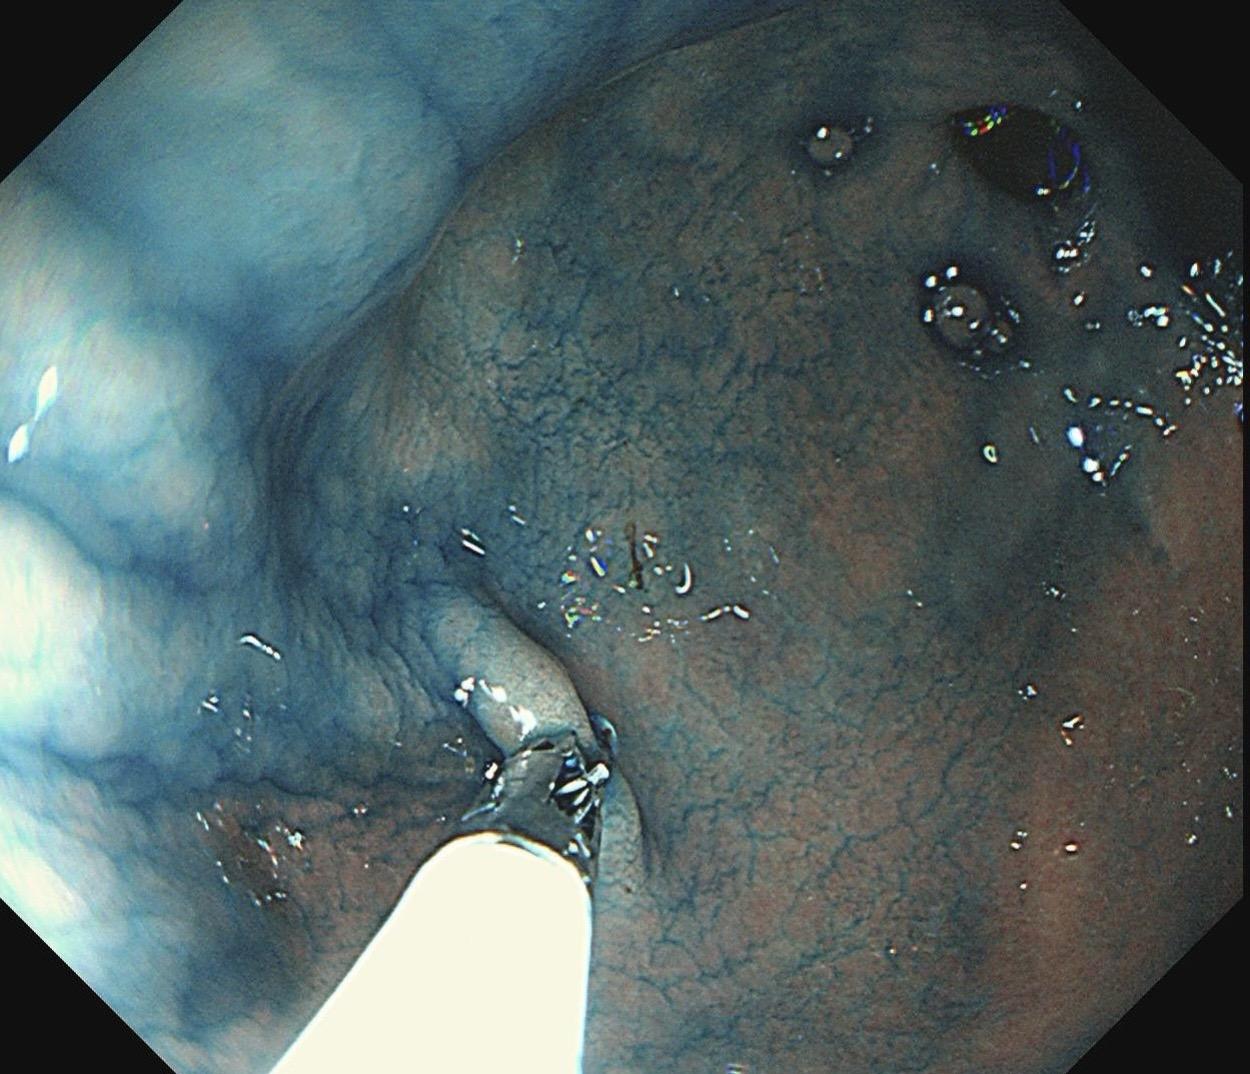

小小的糜烂一枚。这样的病灶,就算结果是阴性的,也很有意义~